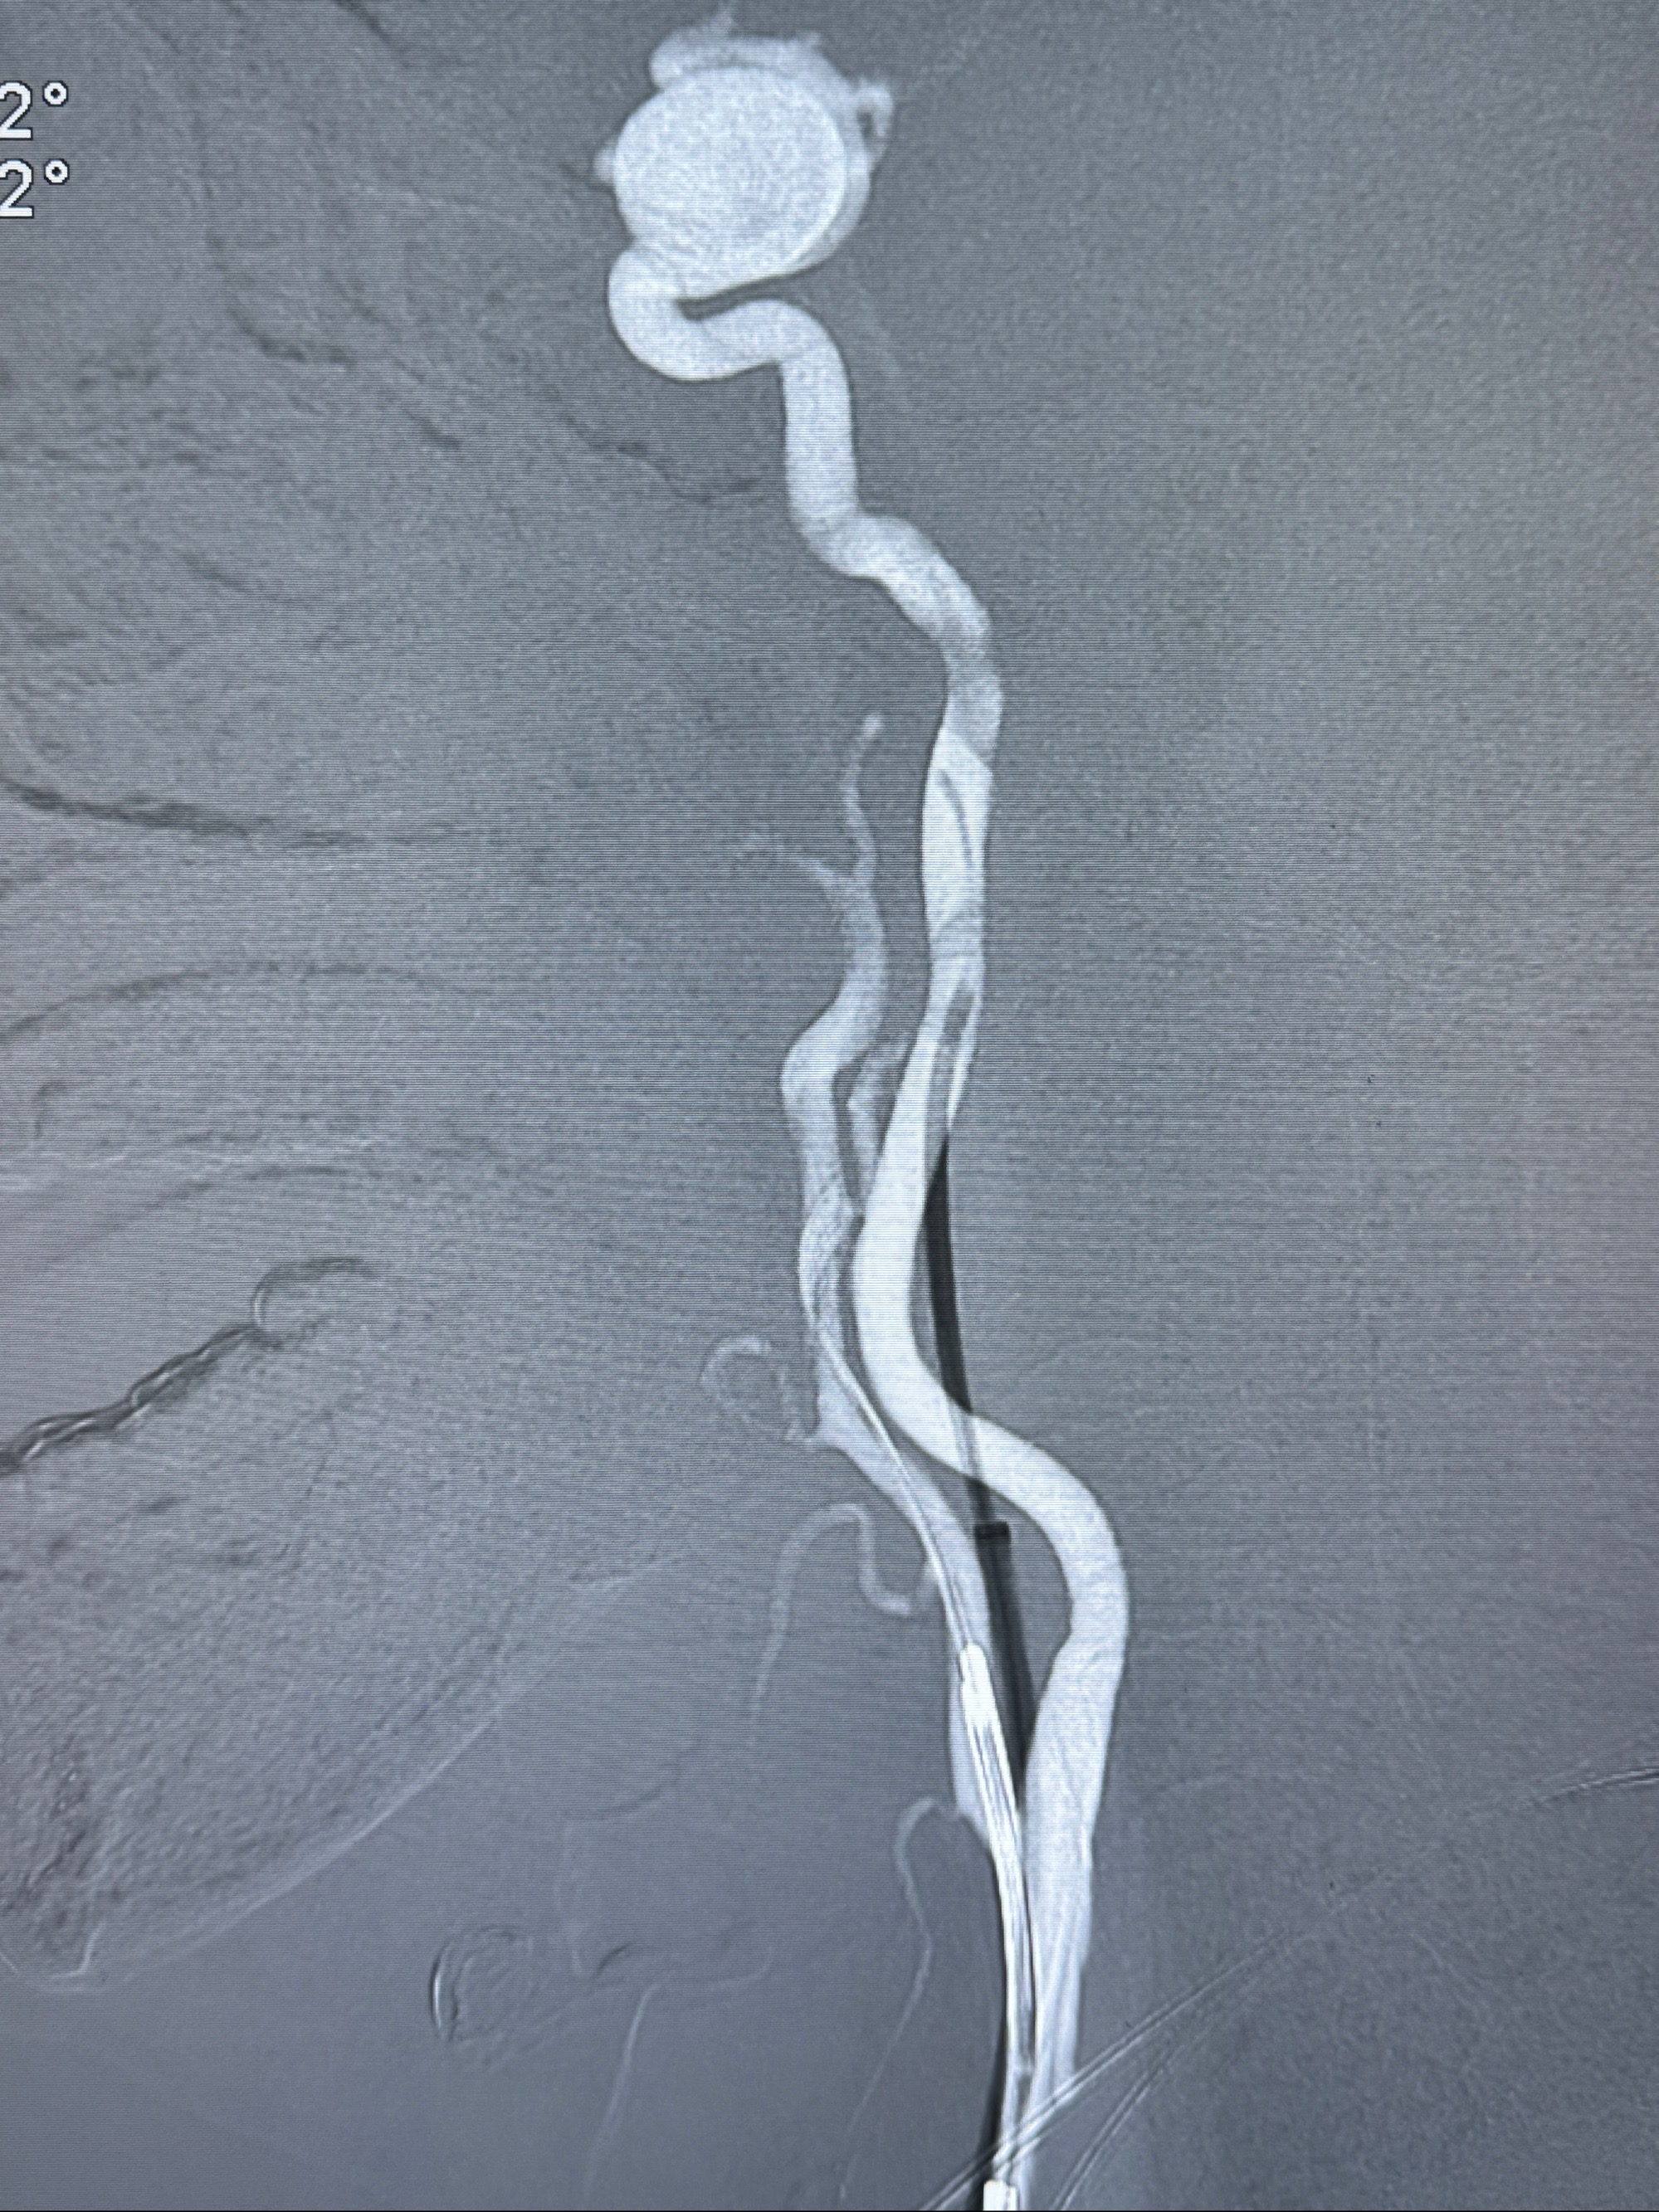

2023-12-18全麻下行DSA➕密网支架植入备弹簧圈辅助栓塞

手术开始了,088导管在MPA及泥鳅导丝引导下进入右侧颈内动脉,灌注盐酸法舒地尔5mg

造影见血管痉挛改变,再灌注盐酸法舒地尔5mg

密网支架微导管在微导丝引导下超选择性插入右侧大脑中动脉

4.5-30mmTurbridge密网支架,于M1近心端打开

透视下支架释放满意

多角度显示支架打开情况

造影显示支架贴壁情况

调整好角度,透视下推挤支架,使支架贴壁

再次造影确认支架贴壁情况